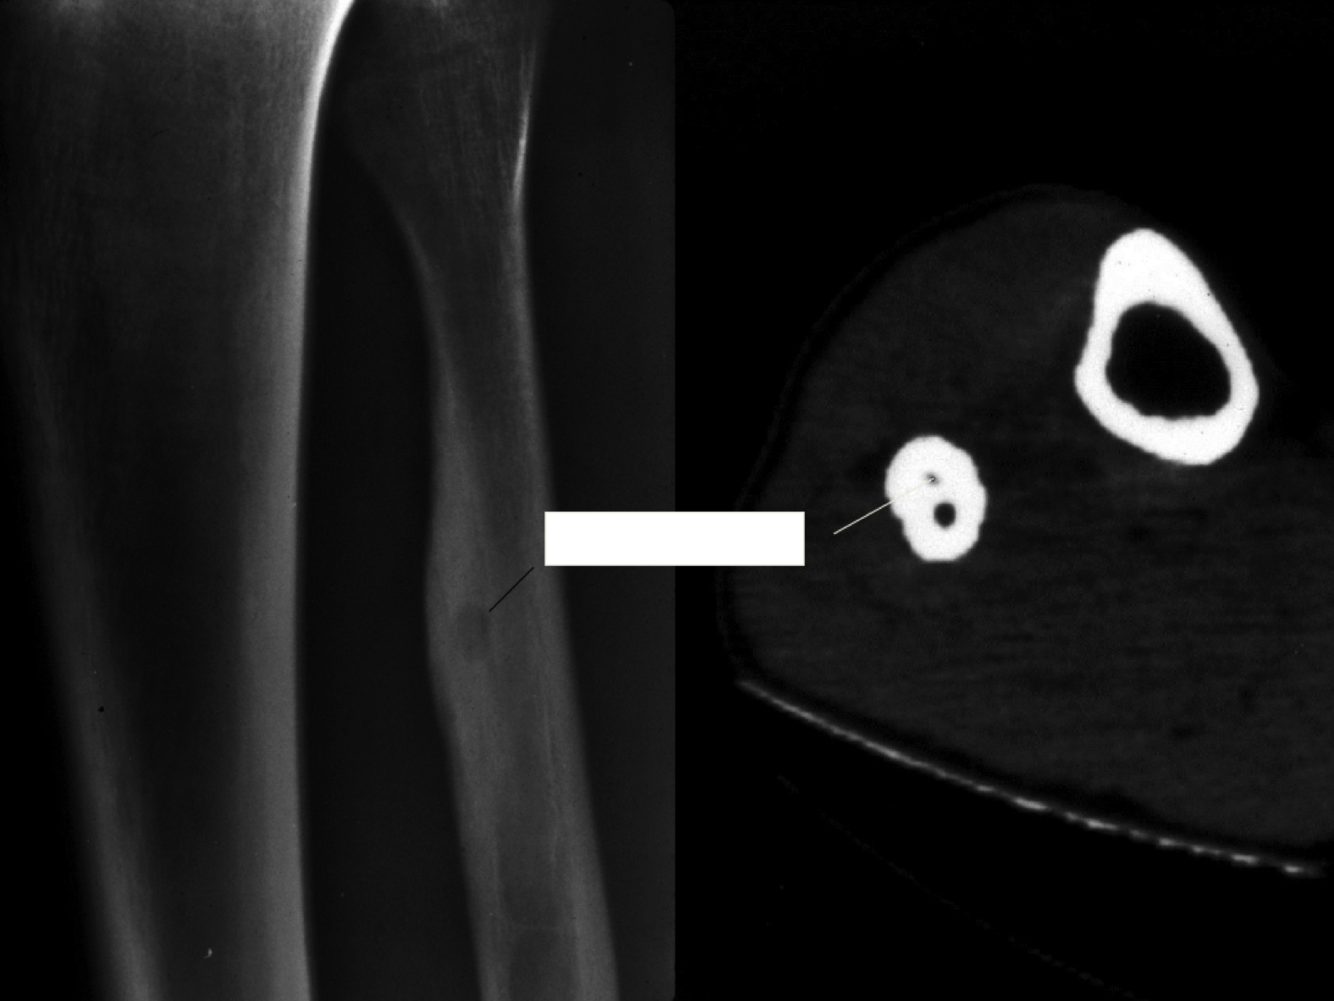

Non ossifying fibroma

Common developmental cortical defect

incidental finding in tibia, femur 0-30

related to eccentric/lytic/peripheral sclerosis

What is this?

Non-ossifying fibroma

Dense fibrous tissue with collagen